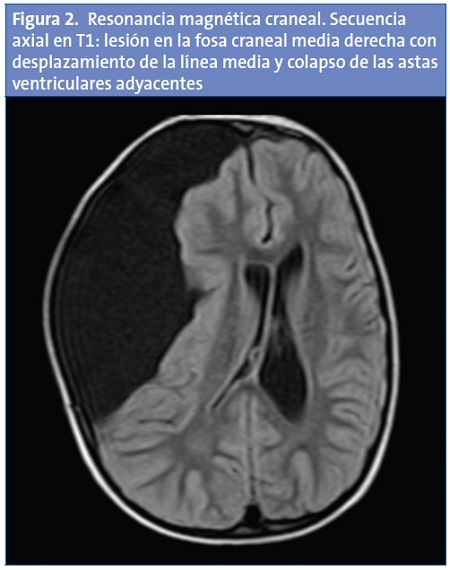

En la TC craneal se visualiza un QA de gran tamaño en la fosa craneal media derecha con desplazamiento de la línea media y colapso de las astas ventriculares adyacentes (Fig. 1), que se confirma en RM craneal mostrando en la región frontoparietotemporal derecha un contenido hipointenso en secuencias de T1 e hiperintensas en T2; que no se modifica tras el contraste con gadolinio (Fig. 2).